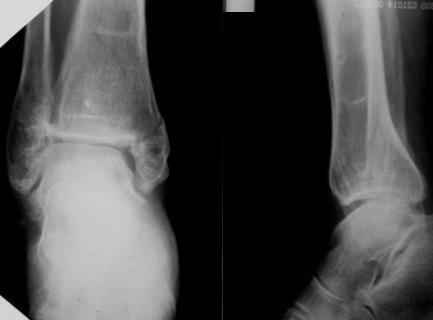

Огромное спасибо всем, кто участвует в обсуждении случая! Приношу глубочайшие извинения и участникам дискуссии и тем, чье внимание просто отвлек своим сообщением. В цейтноте получилось так, что на форум, необоснованно, отправил свои предварительные соображения. Хронология событий следующая. Пришла больная, на руках тот снимок в гипсе, который я выложил. Рассказала, что в 1999г. ломала на этой-же голени обе кости в средней 1/3. Травма тоже была неадекватно низкоэнергетическая - стояла на остановке, шагнула, оступилась - оскольчатые переломы обеих костей. Пластина на большеберцовую. Сросталось долго, линии перелома прослеживались на протяжении 5 лет. Теперешний перелом после того как оступилась в квартире.

Я порассуждал о том, что у нее есть, видимо, системные проблемы с прочностью костей и это МОЖЕТ СУЩЕСТВЕННО ПОВЛИЯТЬ НА ВЫБОР МЕТОДА ОПЕРАТИВНОГО ЛЕЧЕНИЯ, вплоть до артродеза. Предложил начать с замены гипсовой повязки и репозиции для уменьшения отека, столь ее беспокоившего. Которую и выполнил. При попытке R-контроля выяснилось, что кабинет в данный момент обесточен на неопределенный срок. Отправив больную домой я, некорректно по форме, материализовал свои соображения в виде предыдущего сообщения на Форуме.